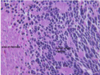

DM T2

DM T2